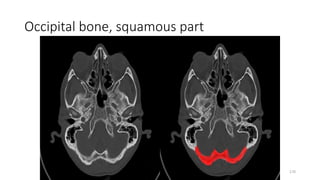

Occipital bone (squamous part)

Occipital bone (squamous portion)

Occipital bone, squamous part